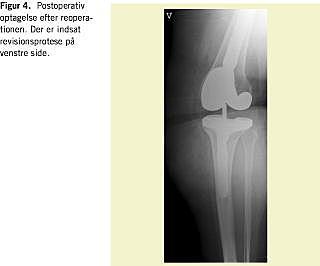

Indførelsen af antibiotika- og tromboseprofylakse ved ortopædkirurgi har mindsket hyppigheden hos overvægtige af alvorlige perioperative komplikationer til alloplastikbehandling. Langtidsresultaterne af alloplastikbehandling af disse patienter er dog generelt ringere end hos normalvægtige (Figur 1, Figur 2 , Figur 3 og Figur 4 ). Englund konstaterede hos meniskektomerede patienter med BMI > 30 kg/m2 en større hyppighed af knæ-OA end hos normalvægtige (BMI < 25 kg/m2 ) [16].